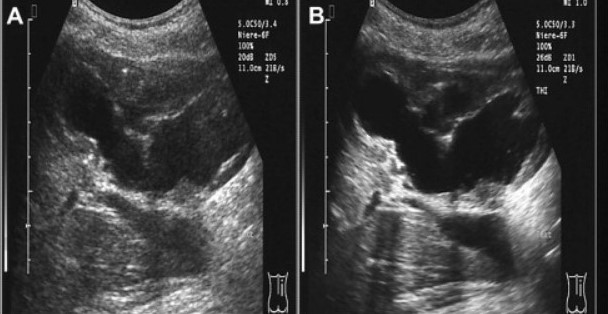

Harmonic Imaging

در این تکنیک، دستگاه به جای استفاده از فرکانس اصلی بازتاب، از هارمونیک دوم سیگنال بازتابی استفاده میکند که حاصل رفتار غیرخطی بافتها است. این روش باعث کاهش نویز و افزایش وضوح تصویر به ویژه در بیماران چاق یا بافتهای عمیق میشود.

از نظر فیزیکی، هنگامی که موج فراصوت از بافت عبور میکند، بافت به صورت غیرخطی پاسخ داده و امواج با فرکانس دو برابر (هارمونیک دوم) تولید میکند. دستگاه این امواج را تشخیص داده و برای تشکیل تصویر با کنتراست بالا از آنها استفاده میکند.